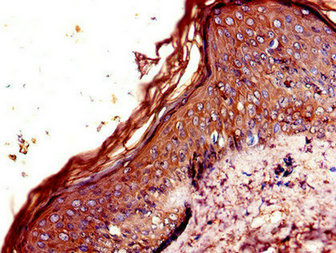

CSB-PA005679LA01HU

Immunohistochemistry of paraffin-embedded human skin tissue using CSB-PA005679LA01HU at dilution of 1:100